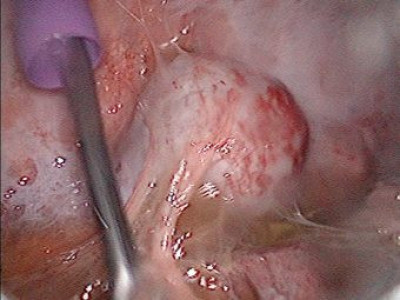

Derrame pleural derecho mas tumor de mediastino posterior